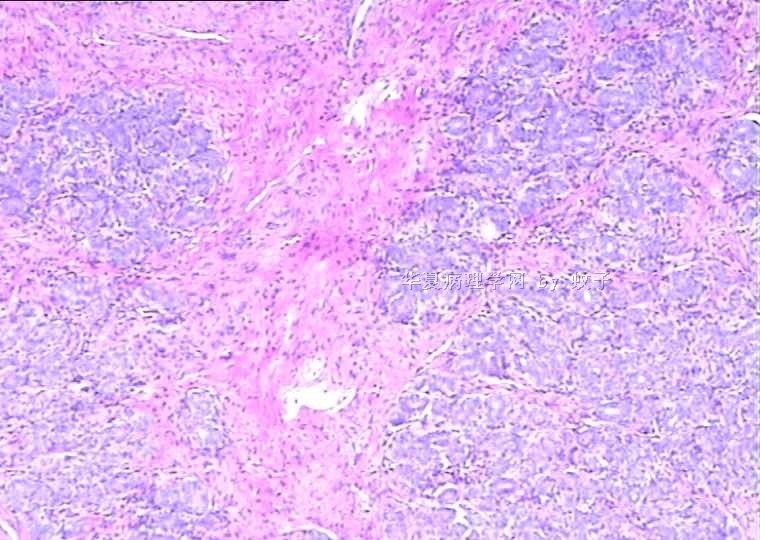

B2156乳腺活检

姓    名: ××× 性别:  女 年龄:  20

简要病史:  右乳包块8年。

肉眼检查:  灰白不整形组织一块,切面灰白,灰红,实性,质韧。

• 乳腺活检图3

图3

标签:乳腺腺病

旺识型腺病

有包膜吗?良性,首先考虑纤维腺瘤(图5、6透明变的纤维支持),其次腺瘤。

无明显包膜,界限较清,

我们考虑腺瘤,(图5,6为混有纤维瘤组织)

腺病瘤(主要成份旺炽性腺病)部分区域为纤维腺瘤(管内型)